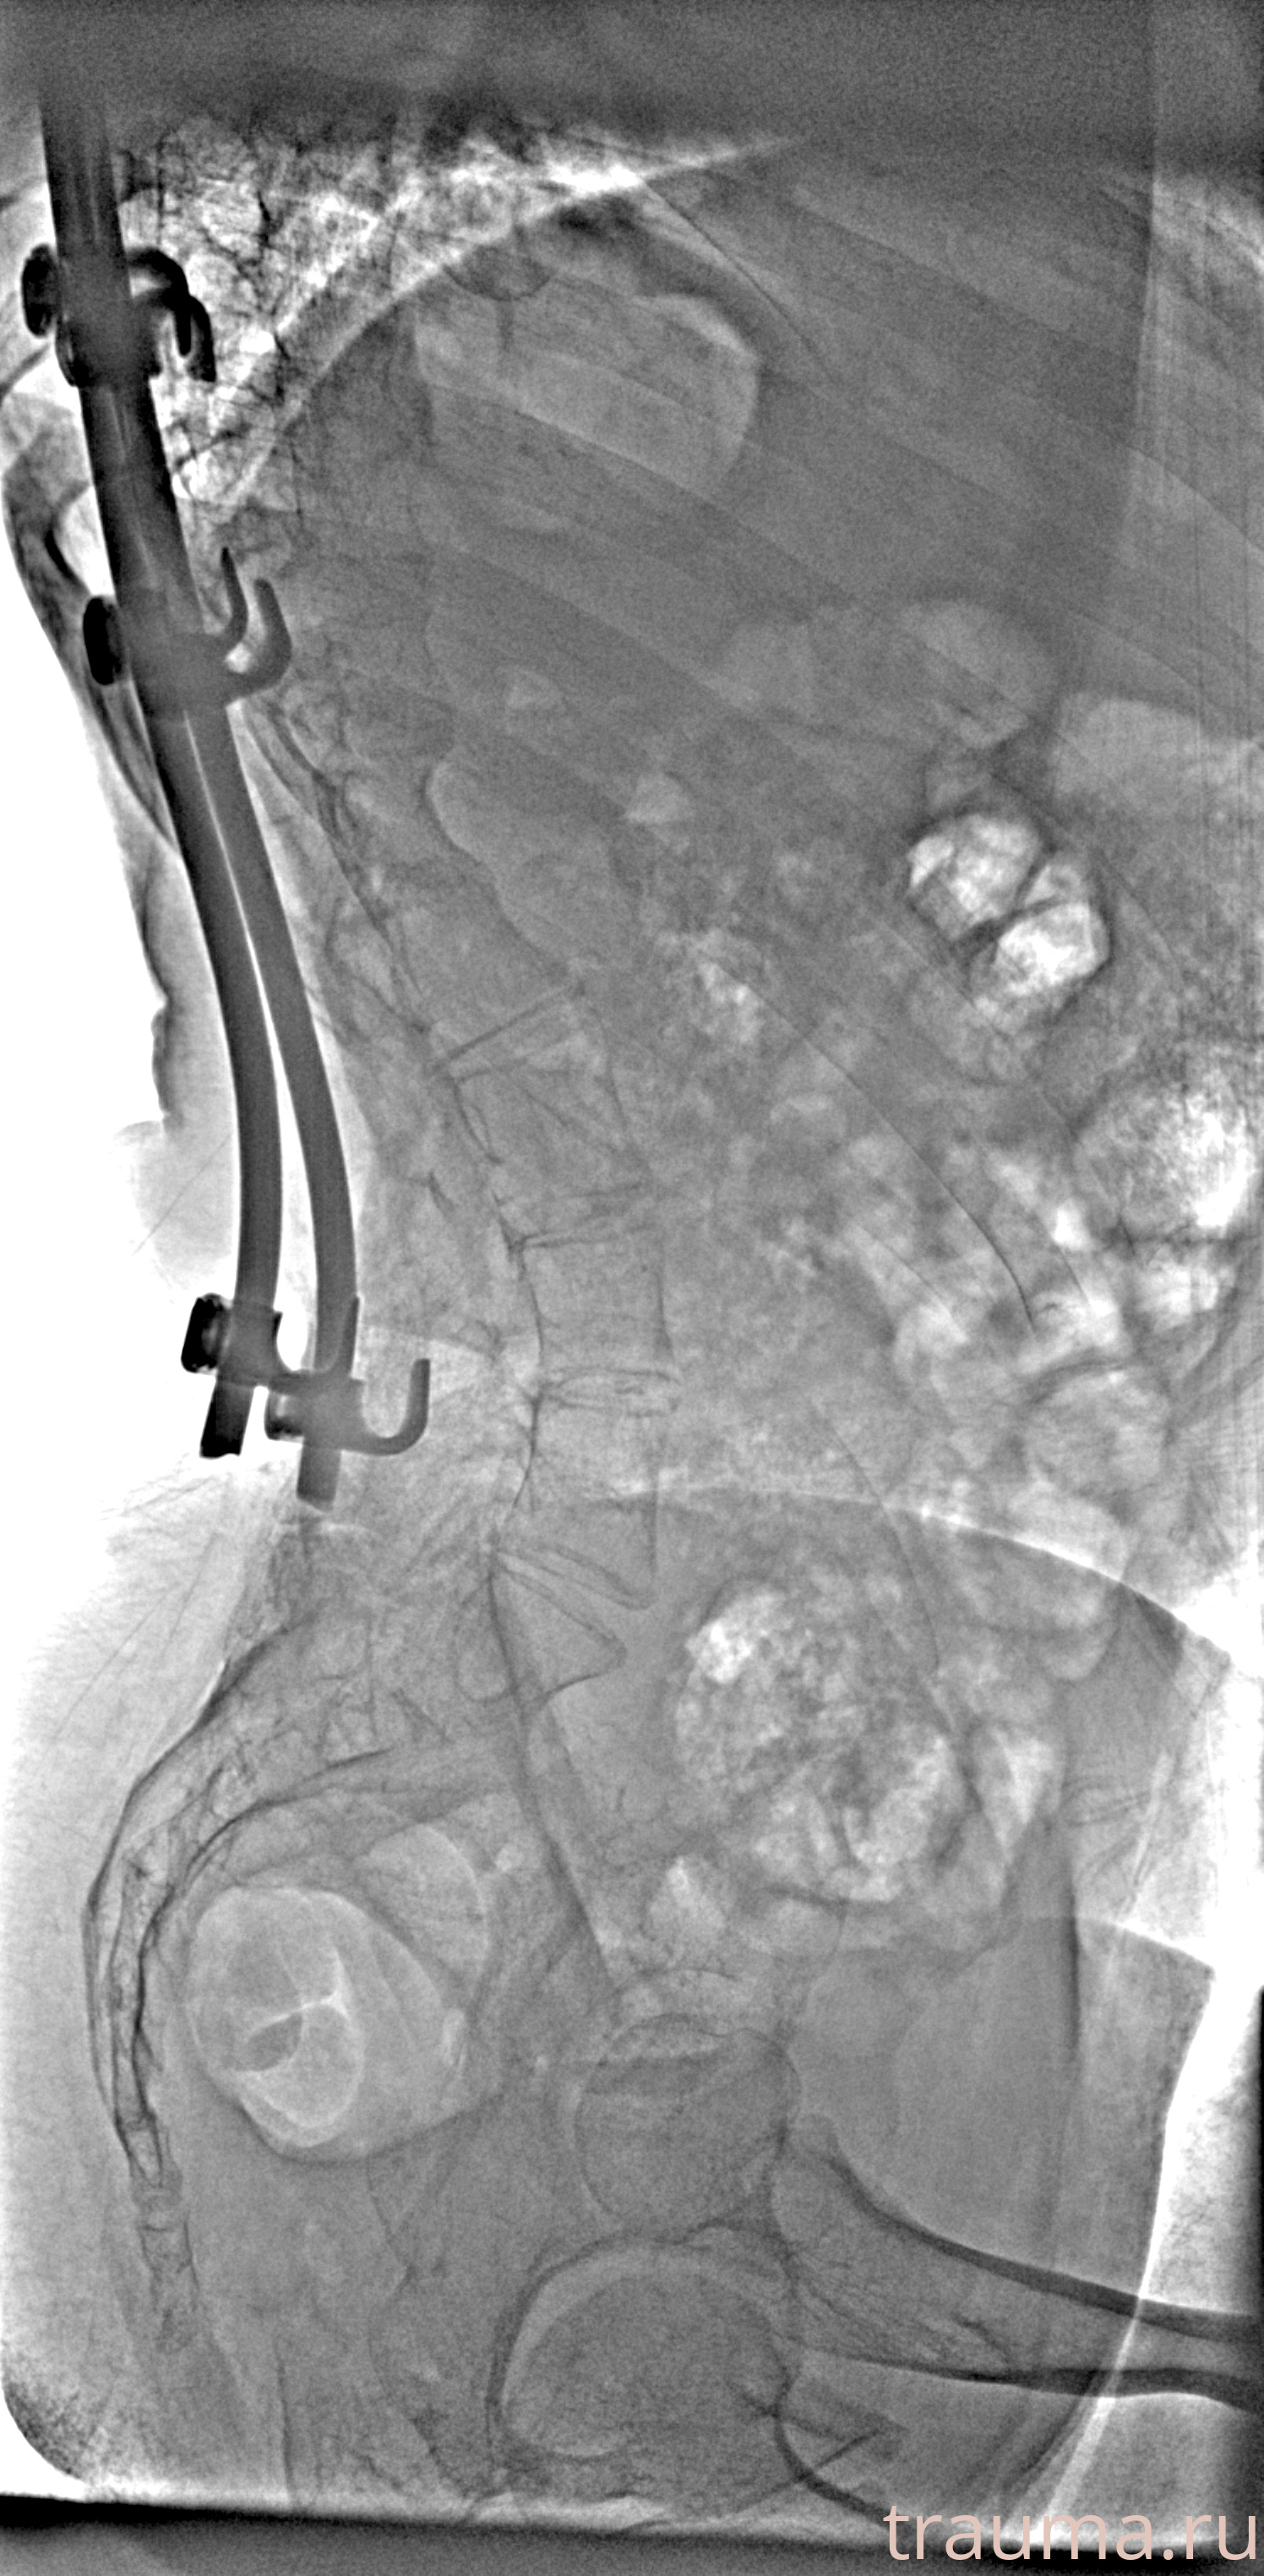

Рентгенограммы

Рентген на дому: по вашему адресу приезжает врач-рентгенолог, травматолог-ортопед с мобильным рентгеновским аппаратом, проводит диагностику травмы или заболевания, делает необходимые рентгенограммы, дает рекомендации по дальнейшему лечению. Получить качественные снимки в домашних условиях возможно благодаря уникальной методике, разработанной МосРентген Центром для института  Склифосовского